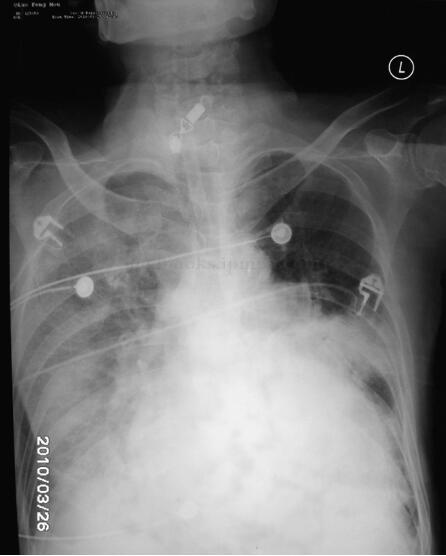

胸部X线片(图003‐1)示:肺水肿并双下肺感染改变;心尖部钙化,不除外室壁瘤可能;双侧胸腔积液,右侧叶间积液;右上肺高密度影。生化结果:心肌酶、肝肾功能正常。D‐二聚体:3129μg/L(0~300)。心电图(图003‐2)示:窦性心动过速,右束支传导阻滞,陈旧性前壁心肌梗死。超声心动图(图003‐3~图003‐5)显示室间隔破裂穿孔(因血栓封堵,无分流):室间隔中间可见两处回声缺失,直径均约为0.4cm,其左室面血栓形成。彩色多普勒:未见明确过隔分流。左室腔中间‐心尖段可见两块不规则形中低密度团块影附着,团块部分相互连接,两团块大小分别为5.4cm×2.95cm、6.1cm×1.23cm。

图003‐1 胸片